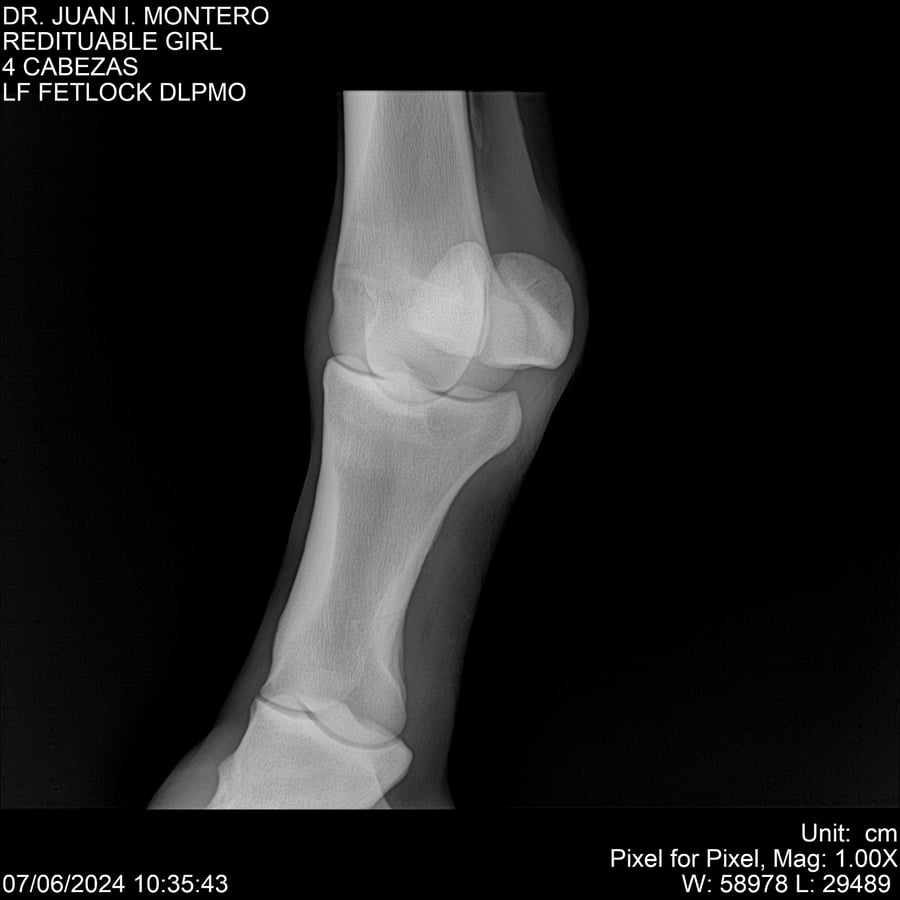

LOTE 19, REDITUABLE GIRL Lote Anterior Volver al remate Lote Siguiente Ficha Contacto Montevideo - Ficha del Lote Identificador: #281096 Categoría: Yeguarizos Montevideo - 79 Visualizaciones ClicData Contacto Empresa: Abelenda N. R., Walter Hugo Nombre*: Teléfono* : E-mail* : Mensaje Enviar Registrese gratis Este contenido Exclusivo está disponible sólo para usuarios registrados Ingresar